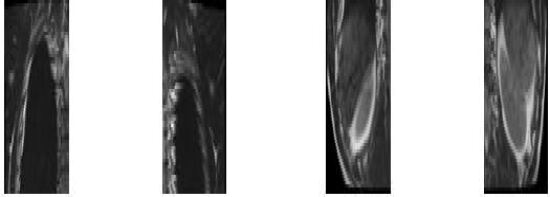

Figure 2: Splitting a 2D image slice for a human spine

Initially, the 2D2𝐷2D slices are split in 4 sub parts as shown in Figure 2 for a human spine, and the data set in divided in two parts. We use single instruction multiple data architecture using 8 logical cores. In parallel, for each block of sub-image, a 3D3𝐷3D matrix is created which is filled with the corresponding data leaving the specified slice gap in between slices as specified for each set as shown in Figure 3. Then edge preserved kriging interpolation is used to generate the 3d subimages. If we want to visualize these sub-images, then we can apply marching cube with color map and visualize the images as shown in Figure 4 and the complete 3D image for visualisation of full spine is as in Figure 5.

Figure 3: Sequence of original 3D sub-images with missing data for a human spine

Figure 4: 3D reconstructed sub-images for a human spine

Refer to caption

(a)

(b)

Figure 5: Complete 3D visualization for a human spine after joining the eight 3D sub-images: (a) Anterior view, (b) Posterior view [a,b,c,d,e,f,g,h marked on this figure corresponds to the sub-images in Figure 4]